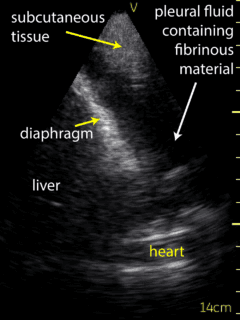

The patient’s right pleural space was assessed by the consultant Respirologist using a VScan device. A small amount of fluid in the right pleural space was noted to be gelatinous in appearance and loculated. Adjustment of the probe to the 6th intercostal space, roughly 10 cm from the spine helped to localize the largest fluid loculation in order to conduct the diagnostic thoracentesis (Figure 3, Video 3).  Following informed written consent, and lidocaine anesthesia in a sterile fashion, an angiocather was introduced guided by the ultrasound location of the largest pocket of fluid.  Approximately 70 ml of bloody fluid was collected.  The patient tolerated the procedure well without complication. Ultrasound post procedure persistence of fluid with several loculations remaining. The collected fluid was sent for routine analysis, cytology, flow cytometry, and culture.